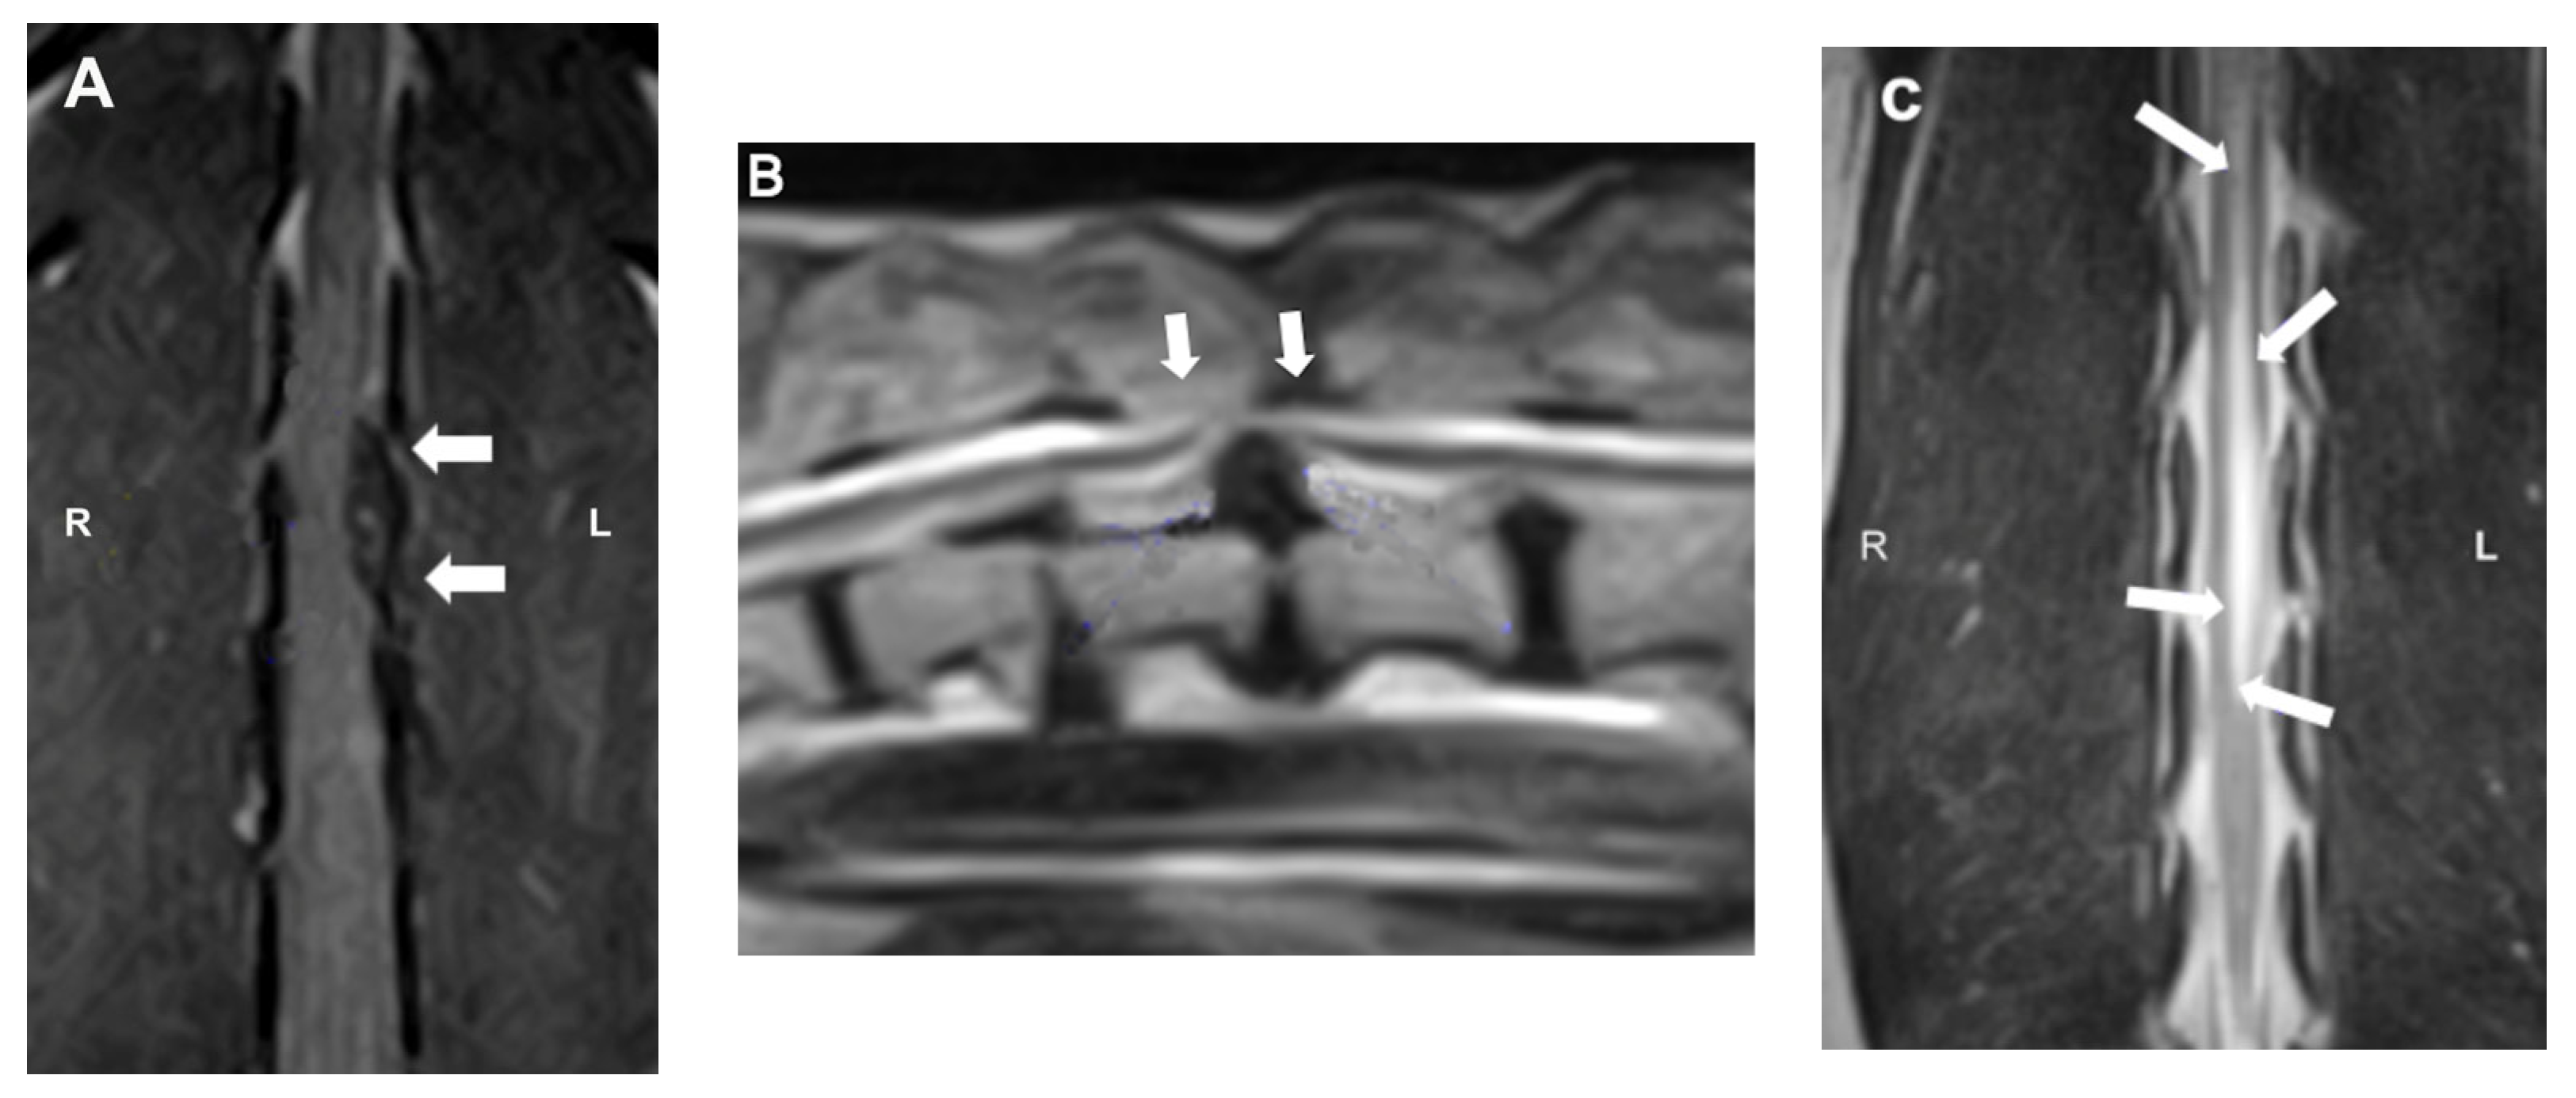

MRI (Figure 5) is currently considered the gold standard for the diagnosis of IVDD in both veterinary and human medicine. With a diagnostic sensitivity of over 98.5%, it provides detailed information on spinal cord compression and intramedullary lesions [41]. Characteristic findings include extradural compression of the spinal cord, visible as loss of the hyperintense signal of the nucleus pulposus on T2-weighted images, and the presence of a hypointense mass (extruded nucleus pulposus) on both T1- and T2-weighted images. The degree of spinal cord compression can be classified (on both CT and MRI) as mild (<25%), moderate (25–50%), or severe (>50%), according to the percentage reduction in spinal cord diameter. In addition, certain parameters observed on MRI images have been associated with unfavorable prognoses. Intramedullary T2 hyperintensity (more than six times the sagittal L2 length), T2 hypointensity, and CSF signal attenuation on HASTE/T2 * sequences have been variably associated with worse locomotor outcome and the development of PMM [43]. Despite its many advantages, MRI has certain limitations, such as high cost, long acquisition times, and lower availability compared to other imaging modalities [38,43].

Figure 5.

Magnetic resonance imaging (MRI) images: (A) dorsal T1W image showing the hypointense compressive material (arrows) at L2-3; (B) sagittal T2W image showing a severe ventral extradural compression in the ventral aspect of the vertebral canal at the intervertebral T13-L1 (arrows); (C) dorsal T2W image showing ill-defined intramedullary hyperintensity consistent with myelomalacia centered over L1–4 (arrows).

CT is considered a first-line option in dogs with acute disc extrusion and degenerated discs because of its speed and affordability. It is particularly useful in young to middle-aged chondrodystrophic dogs. On the other hand, MRI is preferable in complex cases, as it identifies intramedullary lesions and concomitant pathologies. In conclusion, the selection of the imaging modality should be based on the clinical characteristics of the patient, the availability of the equipment, and the specific diagnostic objectives [44,45].